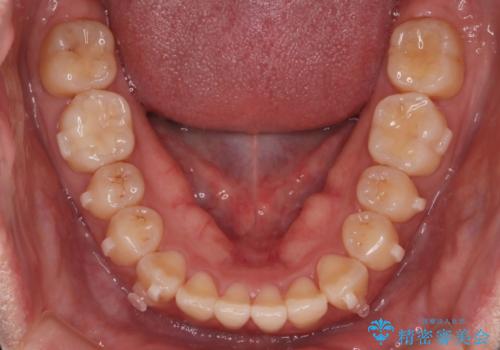

- 上の前歯の捻れを主訴に来院されました。

前歯の捻れとがたつきを改善するために、IPR(歯と歯の間を削る処置)と歯列拡大をすることで歯並びを整えていく治療計画を立てました。

かみ合わせを整えるためにゴム掛けも行いながら、治療していきました。

患者様にマウスピースの使用とゴム掛けを頑張っていただいたおかげでリファイメント(マウスピースの再発注)も1回で終了することができました。